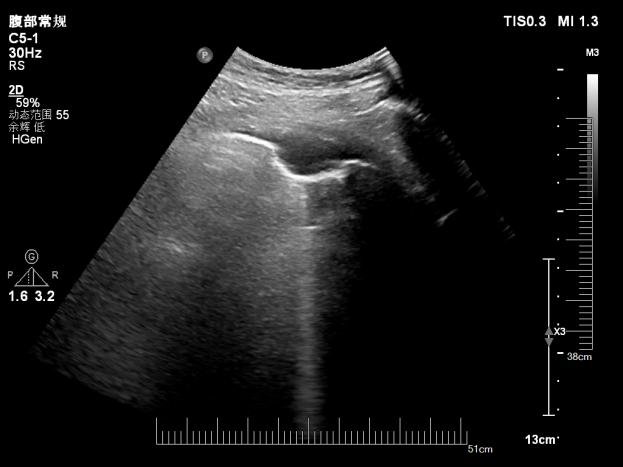

超声显示左侧胸膜结节

超声医学科主任潘国栋与主治医师刘金昊依据超声显示的病变范围,细致规划了穿刺点、进针路线及深度,避开了肋间动脉、神经及病变侧方的肺组织。全程在超声的实时引导下,穿刺针精准到达病变部位,采集了2条病变组织。

经超声引导下避开血管、实时显示穿刺针从进入胸膜结节到击发穿刺针的全过程